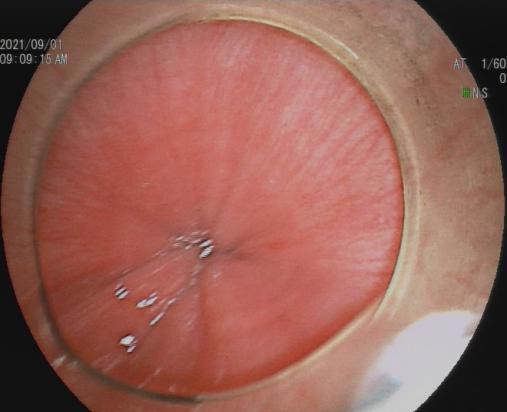

放大内镜下可见不规则微结构 BLI模式下可见不规则微血管

3.早期消化道肿瘤ESD技术

内镜下粘膜剥离术(ESD),具有超级微创、安全性高、住院时间短及费用低等优势,治疗早期胃癌、食管癌、大肠癌等病变,5年生存率超90%。